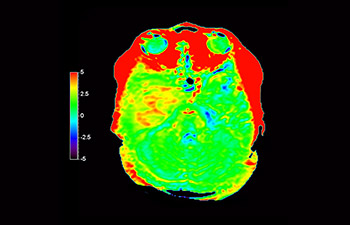

3D APT (Amide Proton Transfer) is a unique, contrast-free, brain MR imaging method addressing the need for more confident diagnosis in neuro oncology. 3D APT uses the presence of endogenous cellular proteins, to produce an MR signal that directly correlates with cell proliferation, a marker of tumoral activity. 3D APT can support trained medical professionals in differentiating low grade from high grade gliomas and, in differentiating tumor progression from treatment effect1.

Glioblastoma

Brain with glioblastoma

with 3D APT